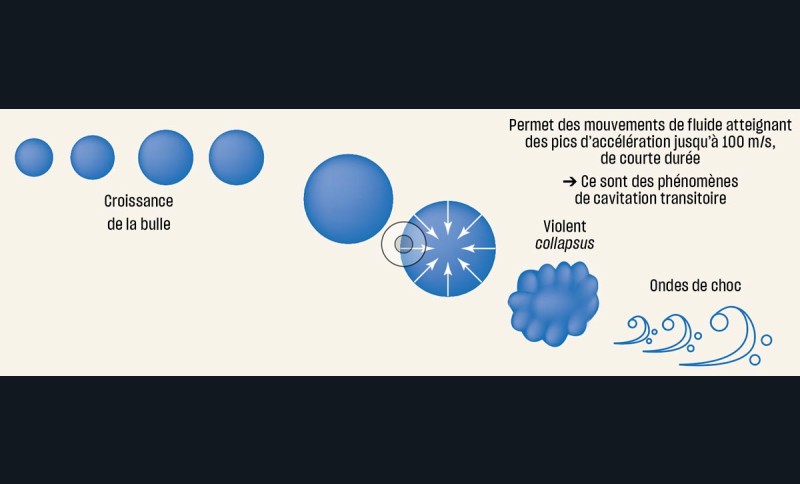

Lors de préparations « laser-assistées », le nettoyage et la désinfection résultent de phénomènes photo-acoustiques, photomécaniques et photochimiques induits au sein de la solution aqueuse irradiée. Le principe physique réside dans la conversion de la lumière laser en chaleur. L’énergie du laser, émise sous forme de tirs (ou pulses en anglais), chauffe la solution et induit un phénomène d’ébullition qui génère l’expansion de bulles de vapeur d’eau (fig. 14). Certaines de ces bulles vont osciller dans le champ acoustique et générer des effets photo-acoustiques. D’autres bulles vont préférer grossir jusqu’à atteindre un volume maximum critique, au-delà duquel la pression interne devient inférieure à celle du liquide environnant. Une fois le tir laser interrompu, les bulles s’effondrent violemment sur elles-mêmes, produisant un collapsus à l’origine d’ondes de choc et de jets de liquide à grande vitesse : c’est le phénomène de cavitation [28] (fig. 15). L’absorption de la lumière émise par le laser Erbium YAG est si intense dans la solution que la vaporisation est immédiate et superficielle. En outre, la très brève durée du pulse (quelques centaines de microsecondes) évite les phénomènes de diffusion thermique.